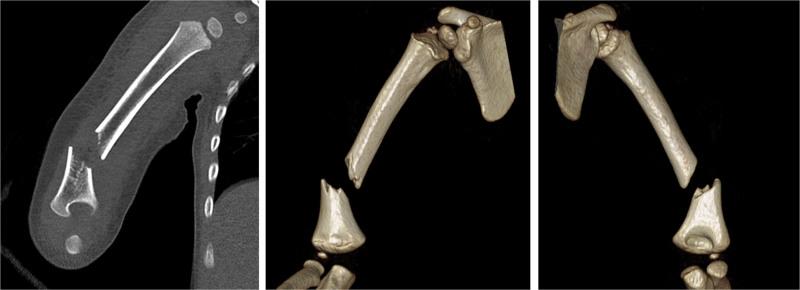

Pediatric distal humeral diaphyseal fractures are rare and challenging to manage due to anatomical and biomechanical complexities. In addition, humeral shaft fractures in adults are often accompanied by radial nerve paralysis (RNP), but there are no studies on the incidence or treatment of pediatric humeral shaft fractures accompanied by RNP in toddlers. The authors present the outcomes of closed reduction and intramedullary nailing using Kirschner wires (K-wires) for high-energy distal humeral metaphyseal-diaphyseal open fractures accompanied by RNP in a toddler. This case report aims to highlight an effective surgical approach and its outcomes in a toddler, providing insights for clinicians facing similar scenarios.

PATIENT CONCERNS

A 23-month-old boy was referred to our emergency room after several hospital visits. He complained of pain in his right arm and presented wrist drop due to a crushing injury by a conveyor belt. A 1 cm open wound was located at the lateral side of the elbow.

DIAGNOSIS

The patient was diagnosed with an open displaced fracture in the distal third of the right humerus on radiographic examination and RNP was diagnosed on the basis of physical examination.

INTERVENTIONS

The authors initially attempted open reduction and internal fixation of the fracture using a Steinmann pin after radial nerve exploration, which confirmed continuity of the normal radial nerve, but fixation failed. Reduction loss and displacement progressed with pin migration the day after surgery, and revision surgery was selected. Closed reduction and intramedullary nailing using K-wires were performed on day 2 after the primary surgery.

OUTCOMES

The patient recovered his ability to extend the wrist and metacarpophalangeal joint approximately 3 weeks after surgery. At the 1-month and 6-month follow-up, the fracture had healed, and radial nerve function had recovered completely.

LESSONS

Intramedullary nailing using K-wires for metaphyseal-diaphyseal fractures of the humerus in toddlers is an effective operative treatment. Among them, high-energy open fractures accompanied by radial nerve palsy might require nerve exploration.